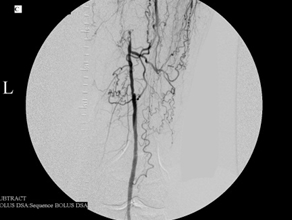

This 75-year-old man’s primary care doctor referred him to my clinic because of left leg cramps after ambulating a few blocks and I found that his left superficial femoral artery was occluded (left column images). Using catheters, wires, balloons, and a covered stent, I restored blood flow through the blocked artery and his problem resolved (right column images).